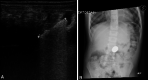

Purpose: Foreign body (FB) ingestions represent a common problem in children. History and physical examination are commonly not enough to diagnose a foreign body ingestion; therefore, conventional radiography is routinely used to detect them. Point-of-care ultrasound is widely used in the emergency department for several diagnostic applications but there are few articles describing the possibility to use point-of-care ultrasound to detect ingested foreign bodies, and the necessary training to get competent in this application. The main objective of this paper is to illustrate the use of point-of-care ultrasound (POCUS) to detect ingested foreign bodies. The secondary objective is to describe a limited training, necessary for emergency pediatricians, to obtain this skill.

Methods: This is a case series of eight pediatric patients who presented to the pediatric Emergency Department (ED), with suspected ingestion of FB, and were assessed with POCUS. Physician sonographers were two pediatricians and three residents in pediatrics working in two Italian Pediatric EDs. All sonographers participated in a 2-day POCUS workshop which included the most common pediatric POCUS applications.

Results: POCUS, performed by emergency pediatricians who participated to a limited training, allowed to always identify the foreign bodies ingested.

Conclusions: We demonstrate that an appropriate and limited training allows pediatric emergency physicians to correctly identify foreign body in the esophagus or stomach. Point-of-care ultrasound in foreign body ingestion in the Emergency Department may allow to prioritize the escalation of care in children and it can contribute to reduce the time to endoscopic management when needed.